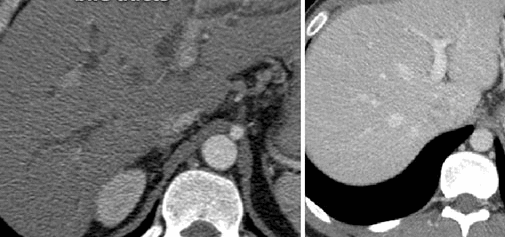

Компьютерная томография демонстрирует поликистоз почек и печени